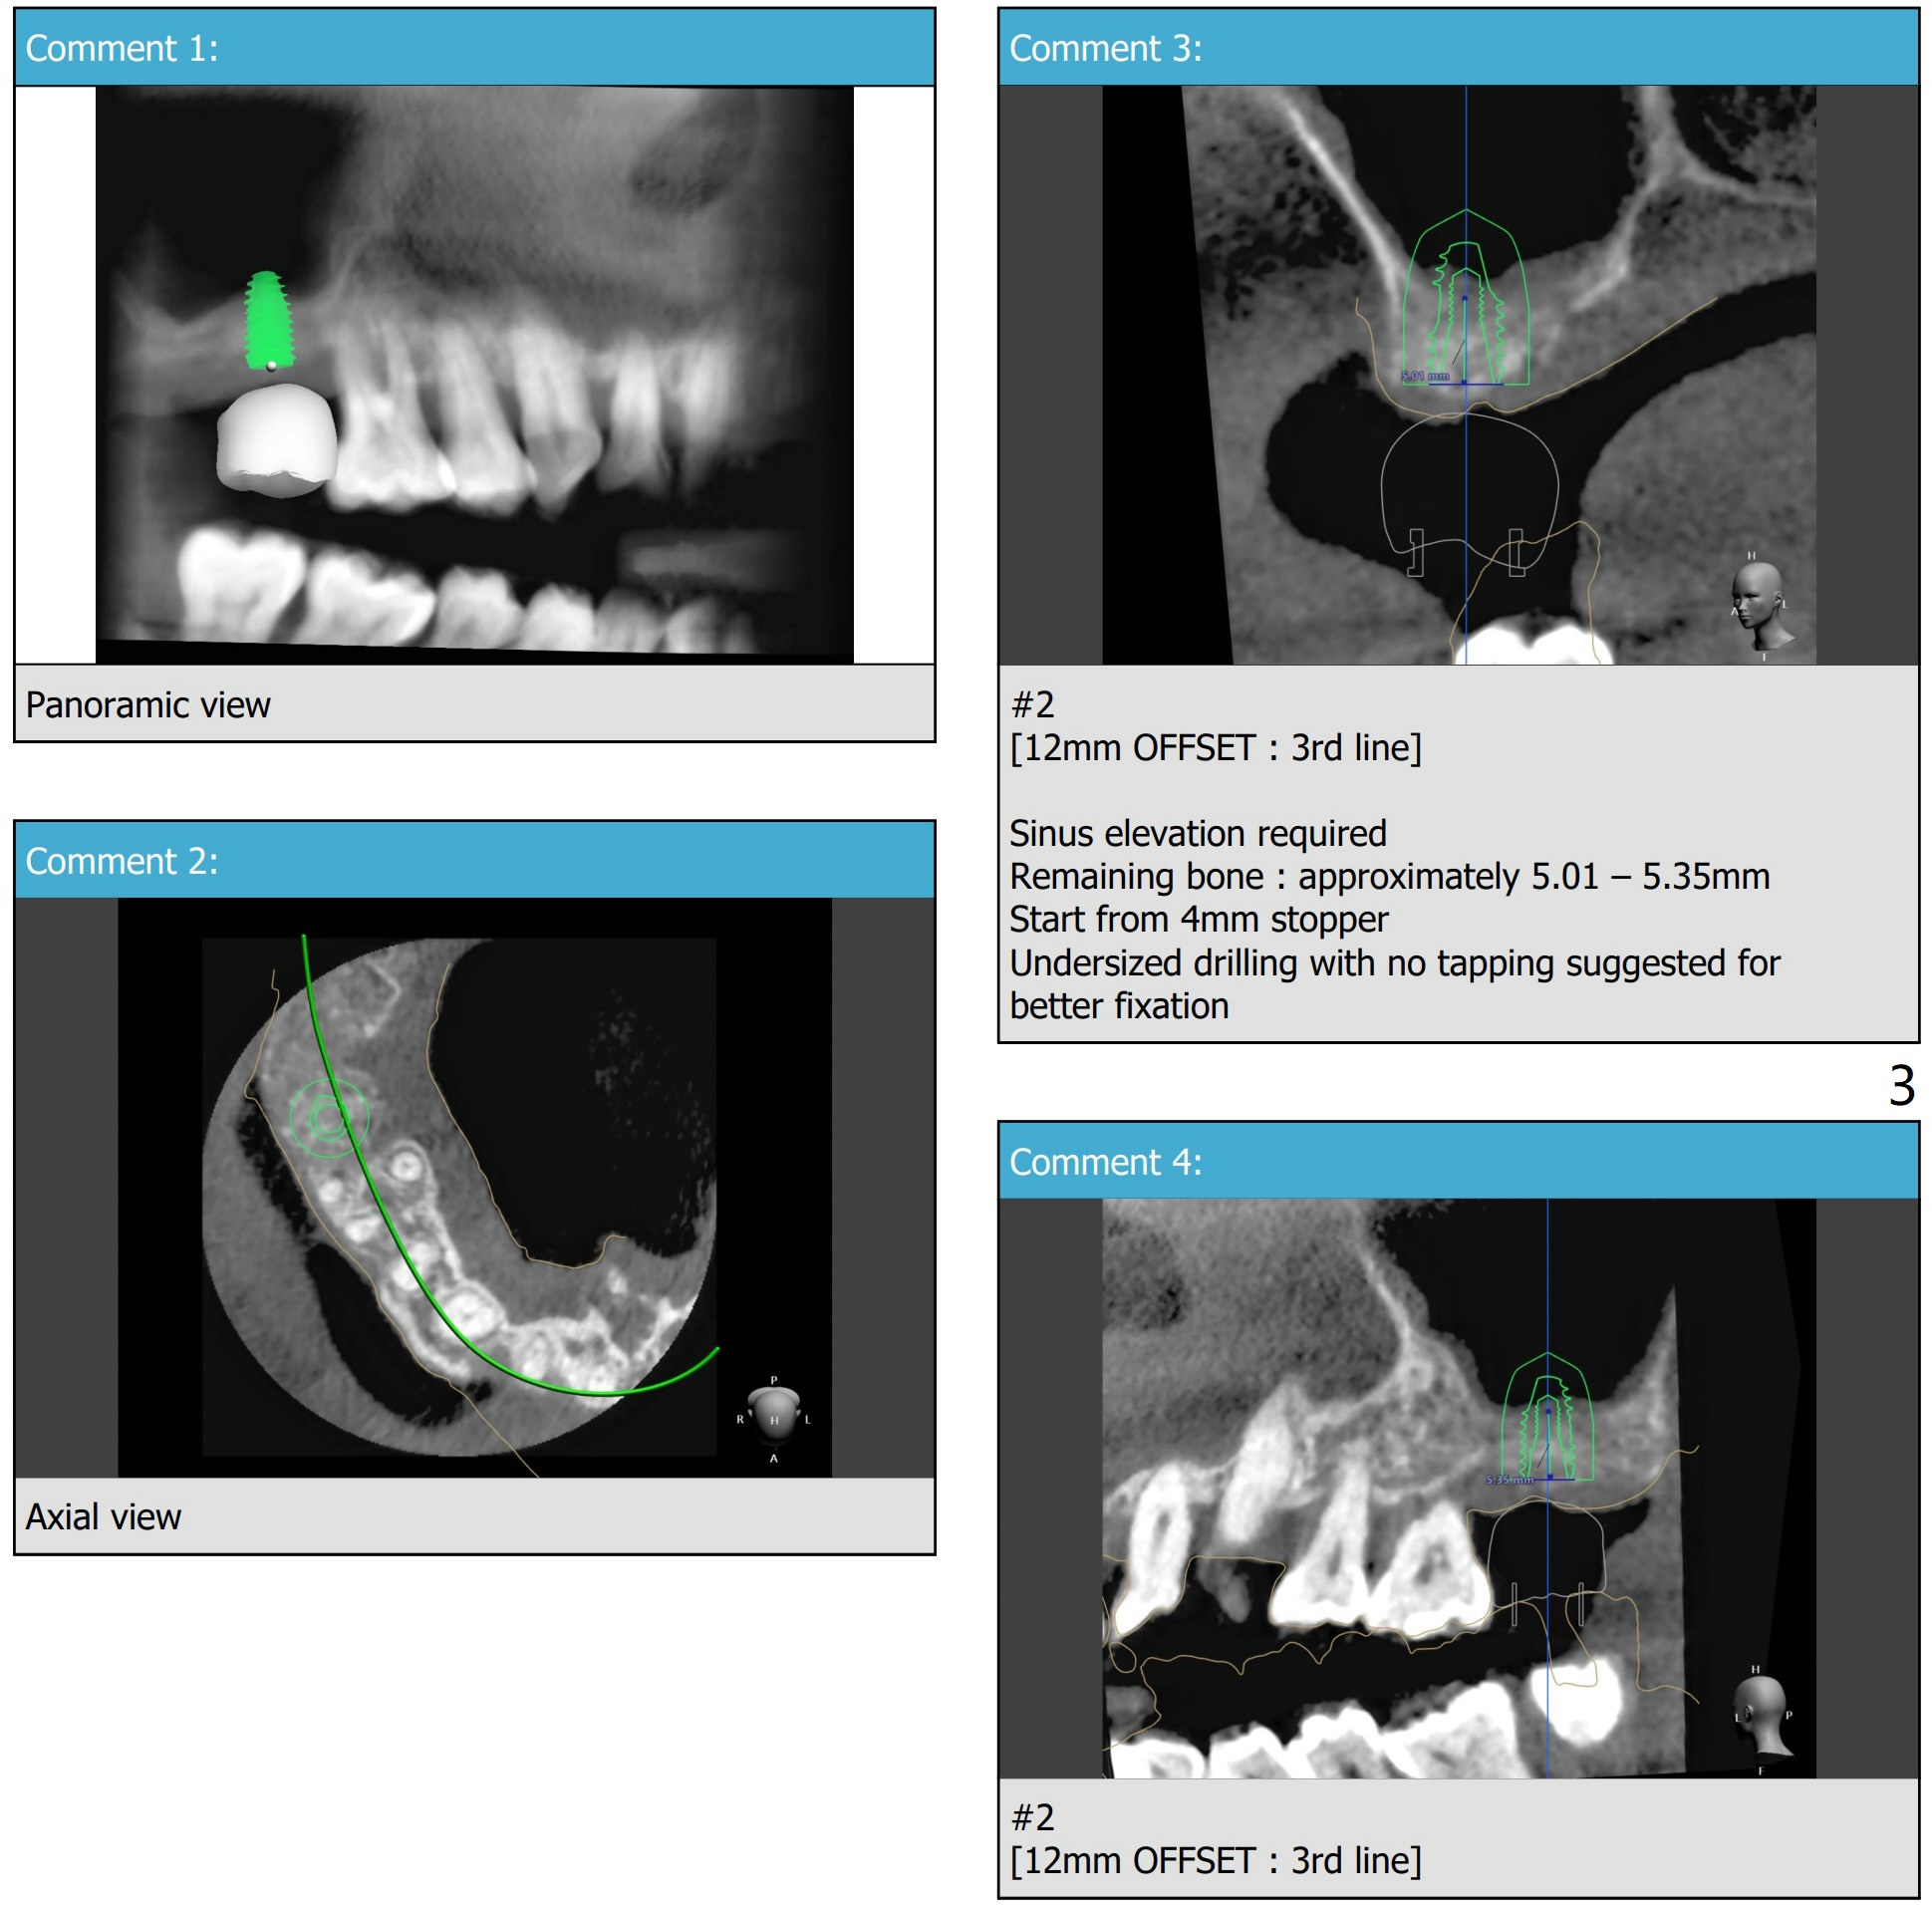

PRF,粘性骨粉用于上颌窦提升

Nearly 5 months post socket preservation. Prepare 4 mm Biopsy Punch. After light use of Tissue Punch to make mark in the gingiva, remove the guide, use the 4 mm Biopsy Punch to harvest the tissue and place the latter in PRF dappen dish. If implant torque is low, place bone graft over the implant, return the tissue to the site and use perio glue for fixation. Finally apply acrylic dressing. Prepare Sinus Approach Kit and 4x10 mm IS dummy implant.